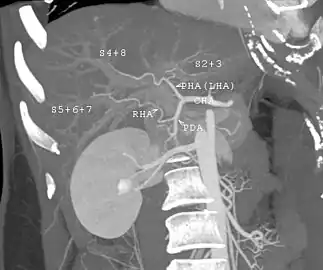

![]() Segments of the aorta, with both suprarenal and infrarenal abdominal aorta | |

The abdominal aorta begins at the level of the diaphragm, crossing it via the aortic hiatus, technically behind the diaphragm, at the vertebral level of T12.[1] It travels down the posterior wall of the abdomen, anterior to the vertebral column. It thus follows the curvature of the lumbar vertebrae, that is, convex anteriorly. The peak of this convexity is at the level of the third lumbar vertebra (L3). It runs parallel to the inferior vena cava, which is located just to the right of the abdominal aorta, and becomes smaller in diameter as it gives off branches. This is thought to be due to the large size of its principal branches. At the 11th rib, the diameter is 122mm long and 55mm wide and this is because of the constant pressure.[2] The abdominal aorta is clinically divided into 2 segments:

- The suprarenal abdominal or paravisceral segment, inferior to the diaphragm but superior to the renal arteries.

- The Infrarenal segment, inferior to the renal arteries and superior to the iliac bifurcation.

The abdominal aorta supplies blood to much of the abdominal cavity. It begins at T12 and ends at L4 with its bifurcation into the common iliac arteries[1] and usually has the following branches: